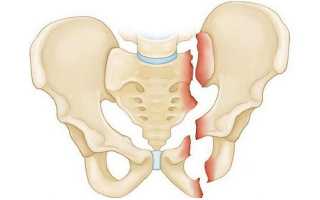

Хирургическое лечение перелома показано при:

- наличии повреждений внутренних органов;

- разрыве лонного сочленения и расхождении лонных костей;

- значительных смещениях костных фрагментов и отсутствии результатов от консервативной терапии.